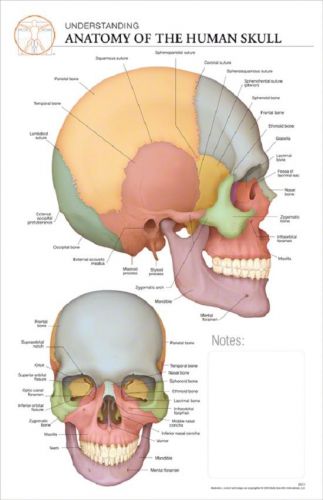

11 x 17 Post-It Anatomical Chart: ANATOMY of the SKULL